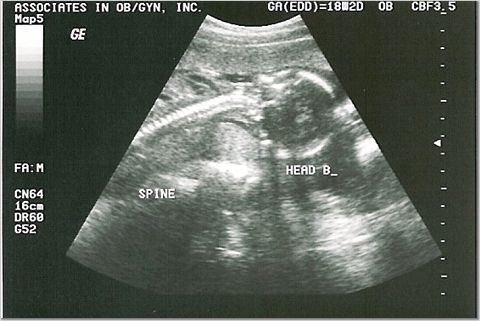

18 weeks - 7 & 8 ounces

We were supposed to find out the sexes, but they were too active for the tech to see!

One of the dancing feet...how cute!